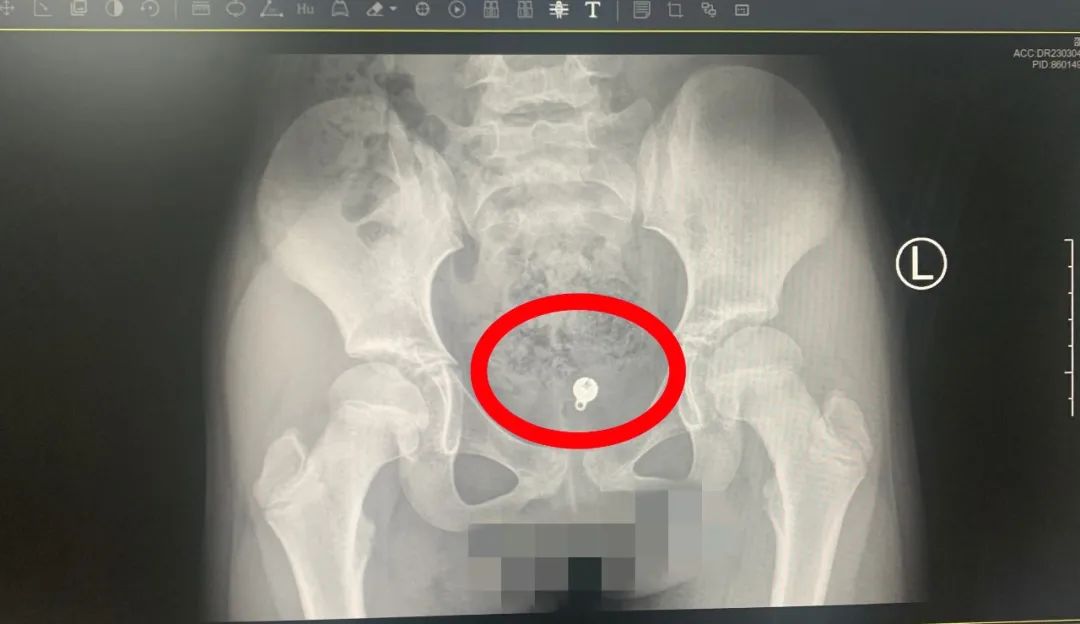

有着丰富泌尿生殖外科诊疗经验的饶品德敏锐的察觉到,这不是简单的阴道炎,需要考虑阴道其他疾病,比如阴道异物,遂紧急安排B超及盆片检查,检查结果出来后,医生和家长惊讶地发现,小女孩的阴道内有一个球形的异物。“这应该就是多年*体下**渗液的罪魁祸首,完整无损的将异物取出,刻不容缓。”饶品德说道。

考虑到异物塞入已经5年,可能部分嵌入阴道内甚至腐蚀阴道壁,如何完整地将异物取出,且不损伤阴道是治疗的关键。有着微创腔镜技术极其丰富的饶品德、熊春凤、朱玮安、曾钦鹿团队决定使用宫腔镜将小琪的阴道异物取出。3月6日,在麻醉团队章征兵、丁玉婷、邱宏的配合下,实施宫腔镜取异物术。术中发现长年的异物导致阴道充血水肿,在阴道的后穹窿处找到了直径约1cm的球形金属异物,经异物钳调整角度,完整将异物取出,没有造成其他损伤。